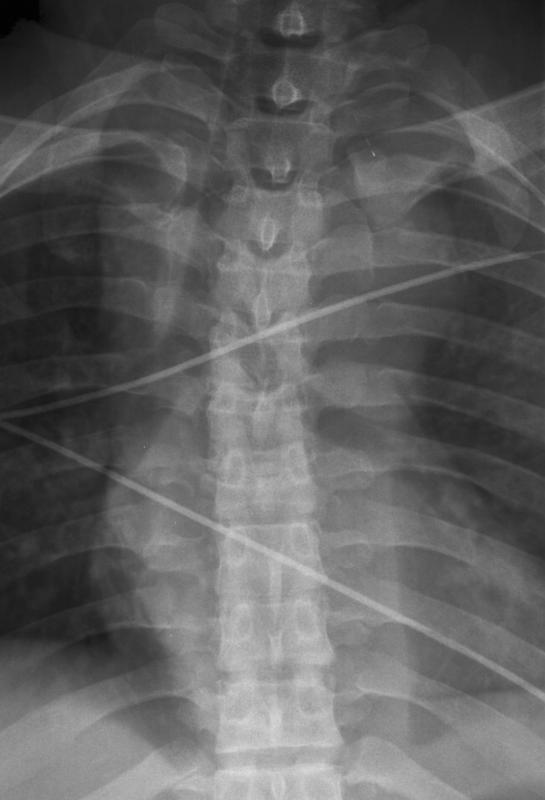

Gallery Blunt Chest Trauma Spine trauma Case 7b

Case 7b